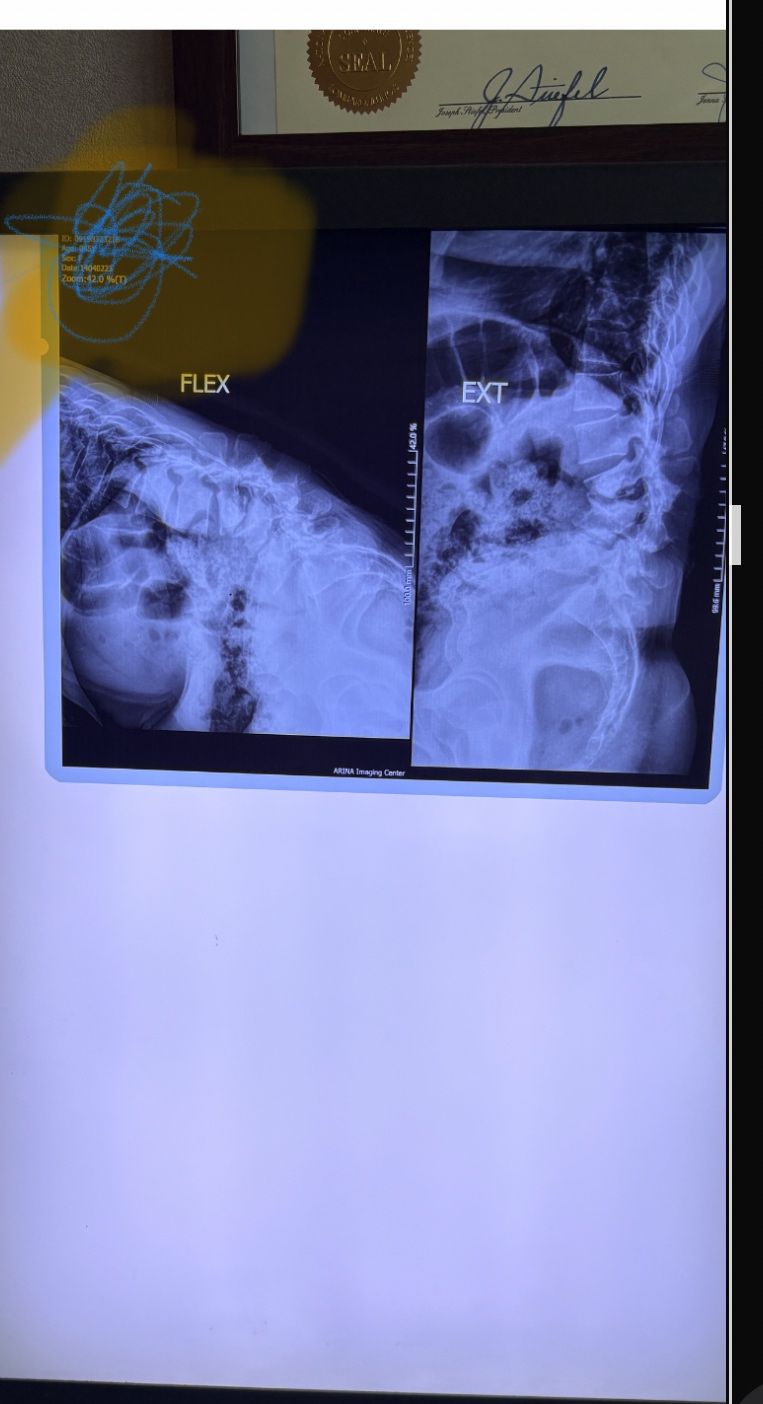

This time presented to my cl with LBP mainly during sleep at night. Just brought me her mri. According to her mri I ordered dynamic L/S X. R.

I didn’t accept her to give treatment. I referred her to her surgeon. What are your findings in her mri and X. Rays?

Is ant listhesis of L4 unstable or stable?

From several compression fractures we see which of is acute/ subacute and which ones are chronic fx?